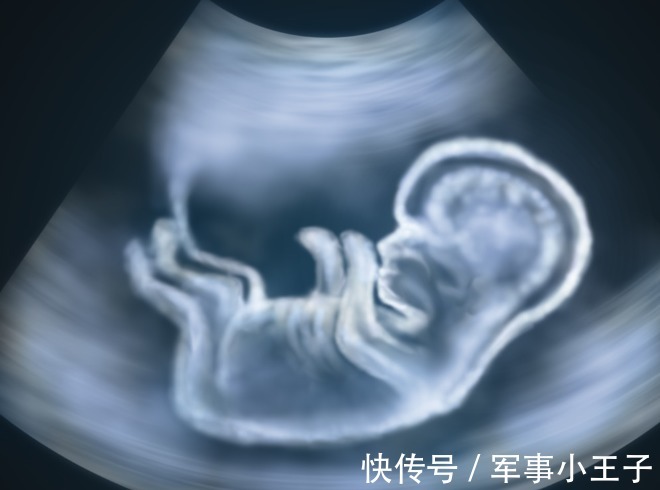

2、心室内的微小钙化灶

什么是心室内的微小钙化灶?

这个在孕检指标里面显示的词是:胎儿心室内点状回声。

发生率:1.5%-4%,亚洲女性发生率更高。

左心室:88%,右心室:5%,左右心室:7%。

当你的大排畸报告显示有心室内点状回声,不用太担心,因为95%在孕晚期都会消失。

文章插图

尤其是,如果只是左心室有,右心室没有,更不需要担心。大多数左心室内点状强回声会随孕周增加而缩小,回声强度也逐渐减弱,到足月妊娠几乎完全消失。

如果左右心室都有,尤其是≥35岁的准妈妈,或合并其他高危因素,存在其他明显的结构或软指标异常,需要做胎儿染色体核型检查及进一步产前咨询与动态随访。